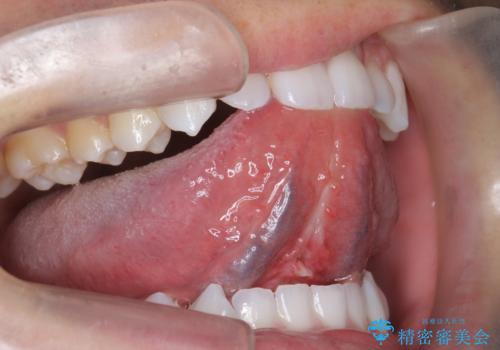

[舌小帯形成術] 滑舌が悪いと言われる

担当医 大元洋佑

![[舌小帯形成術] 滑舌が悪いと言われるの症例 治療前](https://seimitsushinbi.jp/wp/wp-content/uploads/2021/04/6967fe8897ed5d58bc76b5d20bc3d7c8-500x350.jpg?v=1617933505)

![[舌小帯形成術] 滑舌が悪いと言われるの症例 治療後](https://seimitsushinbi.jp/wp/wp-content/uploads/2021/04/IMG_0024-500x350.jpg?v=1617933557)